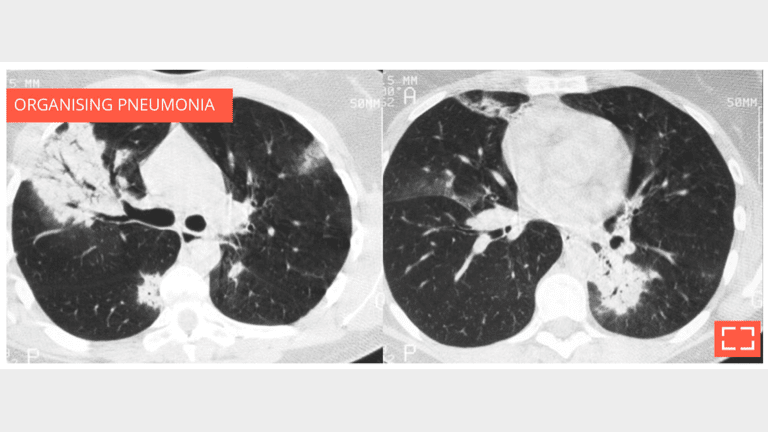

Bilateral subpleural alveolar consolidation with air bronchogram, in a patient with chronic cough.

• Note whether the foci migrate between the two scans, strengthening the argument for organising pneumonia.